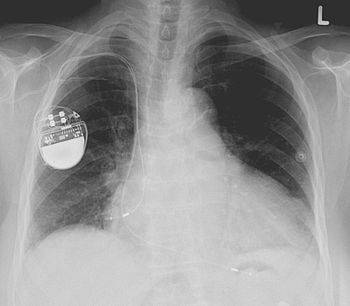

While she stumbles through the drama of her father’s slow deterioration into dementia and death, she struggles to find a way to remain his faithful daughter as she seeks desperately to find a doctor who will turn off his pacemaker and end his suffering. The search is no easy task: bitterly, she admits that in the face of old age “medicine looked more like the enemy than the friend,” as the option of turning off the pacemaker is continually rejected by her father’s cardiologist.